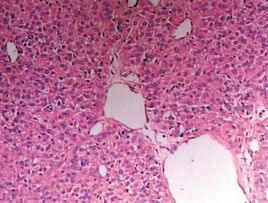

神經內分泌腫瘤CGA廣泛存在於神經內分泌細胞,幾乎所有類型的神經內分泌腫瘤均出現CGA水平升高。經手術治療的神經內分泌腫瘤,血漿CGA水平降低。血漿CGA不僅可作為神經內分泌腫瘤輔助診斷的腫瘤標誌物,還可作為腫瘤發展進程的動態監測和預後指標,用於監測腫瘤的發展與轉移。

CGA作為神經內分泌活性的強有力指標,在心血管疾病中作用的研究也較多。慢性心力衰竭患者CGA水平增高,其增加幅度與心力衰竭嚴重程度相關,心力衰竭患者血漿CGA及B型利鈉肽水平明顯升高,與心功能NYHA分級、心力衰竭嚴重程度密切相關,CGA是慢性心力衰竭患者病死率的獨立預測因子。心肌梗死後血漿CGA水平與病死率增加相關,其水平每升高10ng/mL時的死亡風險比為1:22,經校正後血漿CGA水平仍與病死率相關,其水平每升高10ng/mL時的死亡風險比為1:17。提示CGA的升高與心肌梗死後長期病死率相關。心肌組織能分泌CGA,證實CGA水平與腦鈉素水平呈正相關。採用免疫組織化學方法證實擴張型心肌病患者中CGA水平明顯升高。作為神經內分泌活性指標的CGA,在擴張型心肌病患者的心肌及血循環中表達均升高,提示CGA可能參與了擴張型心肌病的發生,並與其病程相關。

血漿CGA升高對前列腺癌病程有預測作用。前列腺癌組織中存在明顯神經內分泌分化,分化的神經內分泌細胞產的CGA可作為血清標誌物用於前列腺癌的診斷。但CGA是神經內分泌細胞分泌的一種特殊產物物,不為前列腺癌所特有,在其他神經內分泌腫瘤中也會升高,因此臨床上聯合檢測CGA及前列腺特異性抗原,對前列腺癌診斷及預後評價有臨床意義。血漿CGA水平可用於前列腺癌的診斷,尤其對前列腺特異性抗原陰性或伴有遠隔轉移的進展期前列腺癌的監測及診斷有重要意義。